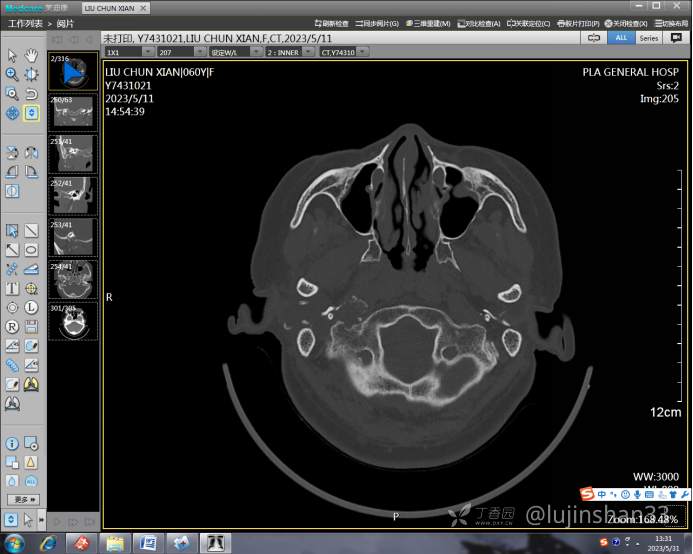

(2023-05-12 10:15,本院)行CT(颅脑)检查提示:右侧颞骨广泛骨质破坏,伴巨大软组织肿块,性质待定,考虑肿瘤性病变,颈静脉球瘤?软骨源性肿瘤?请结合临床及病理进一步明确。